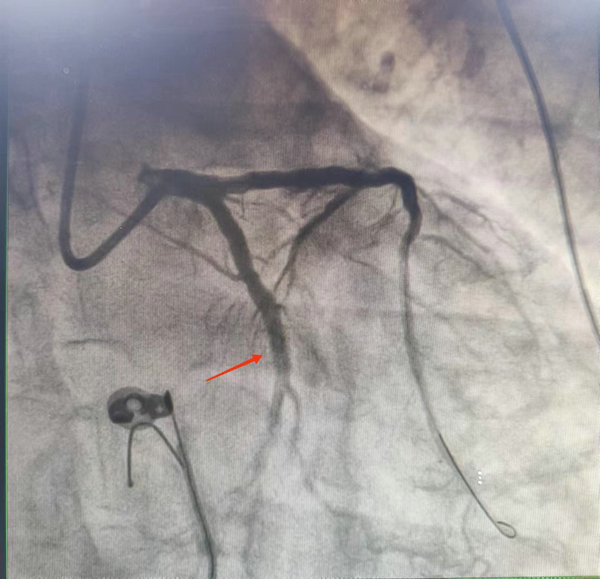

3年前,李师傅因急性心肌梗死被紧急植入3枚支架,但部分血管仍有重度狭窄。李师傅抱着侥幸的心理未遵医嘱进行择期手术。今年1月底,因剧烈的胸闷、胸痛,被120紧急送到当地某三甲医院。经造影显示,李师傅病情极其凶险,冠脉三支严重病变、右冠完全闭塞、前降支原支架近端急性闭塞、回旋支重度狭窄……因手术风险极高,该次急诊手术后放弃了进一步心脏搭桥或心血管介入治疗,仅于前降支近段原支架内扩出一条血流后,建议李师傅采取保守治疗的方式回家修养。

主动脉球囊反搏术支持下的高危冠脉介入手术不仅要求术者有高超的手术技巧,也对手术团队提出了更高的要求。2月下旬,经过充分的术前准备,吴强主任医师、叶凤翔主治医师、石美莉主治医生组成的手术团队在主动脉球囊反搏泵的支持下,于李师傅前降支近段原支架内行药物球囊扩张成形术,防止再狭窄,对重度狭窄的回旋支进行支架扩张。

术后血管恢复供血

整台手术一气呵成,用时1小时左右,术后李师傅转入CCU监护病房,经过心内科医护人员的精心治疗与护理,平稳度过危险期,各项生命体征渐趋正常。1天后,拔出主动脉球囊反搏泵后无特殊不适,遂转入普通病房。

“患者心脏供血最主要的3根血管均存在严重病变,用高压球囊扩张严重狭窄且唯一没有梗塞的回旋支是极其危险的,意味着心脏在10-20秒的时间内会没有供血,患者随时都有呼吸心跳骤停、猝死的风险。此时患者的心脏好比一个体力即将透支的人,却在用尽全力强行拉车,随时都有可能累倒在地。这也是本次手术主要的风险之一。主动脉球囊反搏技术就相当于给车子装上了电动马达,辅助拉车人进行做功运动。高压球囊扩张、放支架的这十几秒全靠反搏泵以秒计时来支撑。主动脉球囊反搏泵会随着心脏跳动有规律地收缩和舒张,产生一种压力,帮心脏往外送血,减轻心脏收缩期后负荷并增加心脏舒张期冠状动脉供血。”吴强主任强调本次介入手术使用主动脉球囊反搏泵的必要性时说。